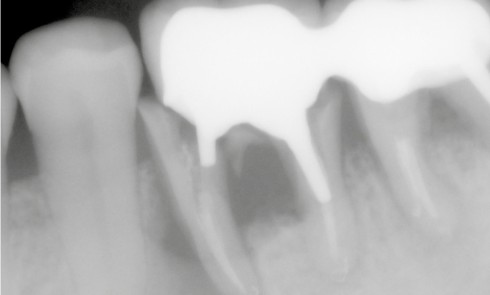

Article réservé à nos abonnés Reconstitutions corono-radiculaires : vers un changement de paradigme ?

Les différentes reconstitutions corono-radiculaires (RCR) sont représentées par des techniques directes (dites par matériaux insérés en phase plastique ou RMIPP)...